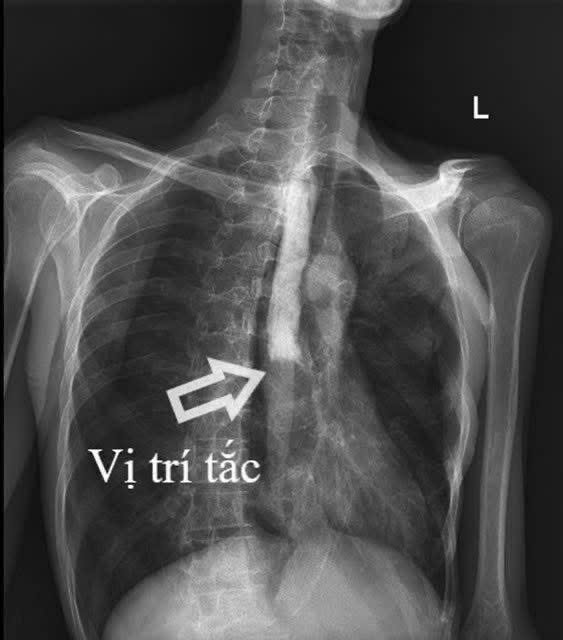

Kết quả cận lâm sàng cho thấy bệnh nhân bị tắc hoàn toàn thực quản đoạn 1/3 giữa, kèm viêm lan tỏa dạ dày, ruột non và viêm phúc mạc. Tổn thương xuất hiện ở nhiều vị trí khiến việc xác định nguyên nhân trở nên đặc biệt khó khăn, với nhiều khả năng như lao, ung thư (lymphoma) hoặc bệnh lý tự miễn (Crohn).